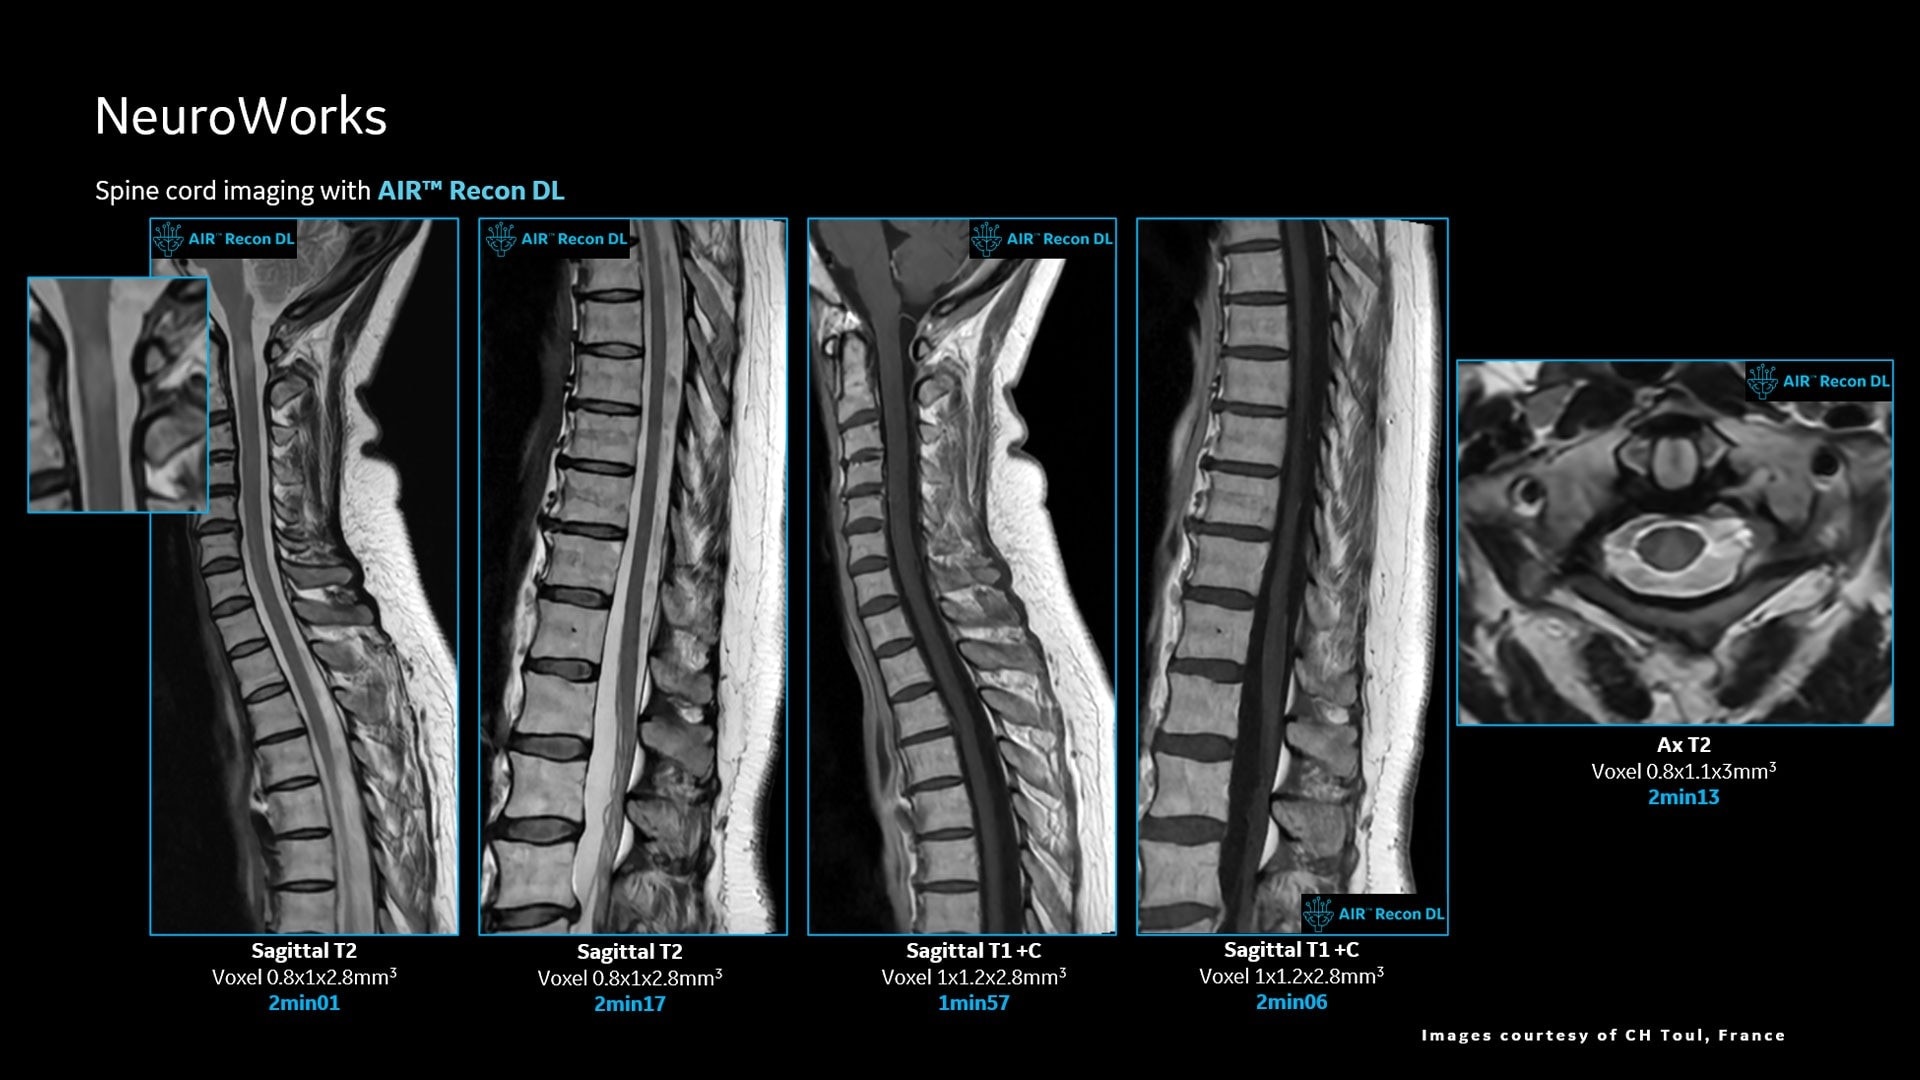

AIR™ Recon DL improves SNR and image sharpness, enabling shorter scan times

Up to 50% faster acquisition time with AIR™ Recon DL

Achieve a 25% efficiency gain with Ultra High Efficiency (UHE) gradient system. Fast, clear Total Digital Imaging (TDI) increases SNR by 25%. Improved IQ in 80% of cases without added time. Acquire higher SNR without a time penalty and get images virtually free of artifact with AIR™ Recon DL.***